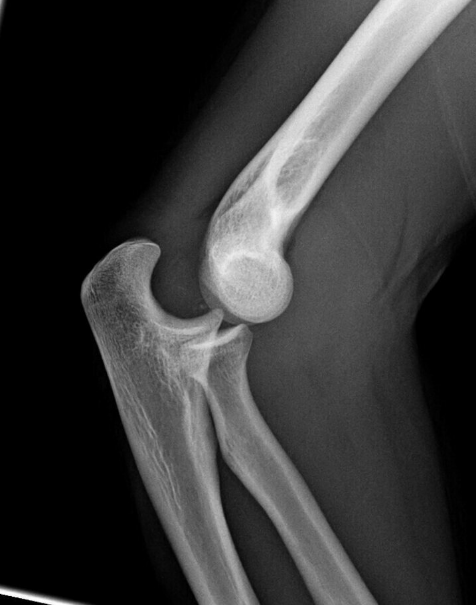

The most common nerve affected by posterior elbow dislocation is _____ nerve

The most common complication associated with elbow dislocation is _____ at the elbow.